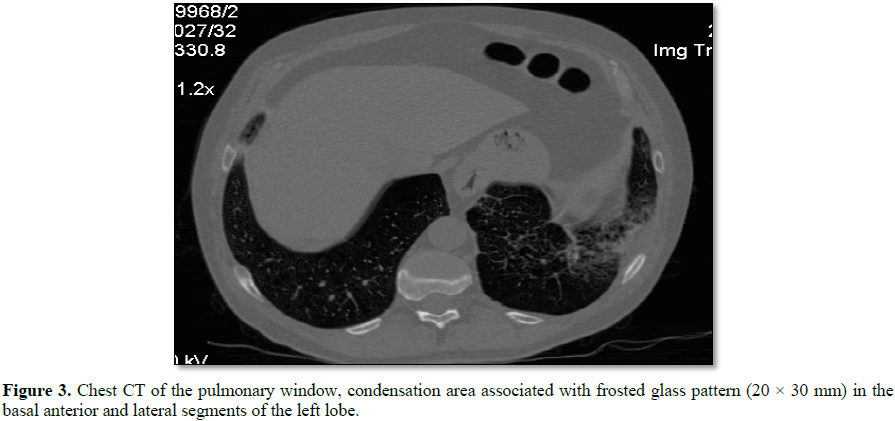

At the level of the anterior and lateral basal segments of the left

lower lobe, a condensation area, associated with a frosted glass pattern, with

linear images is visualized (Figure 3).